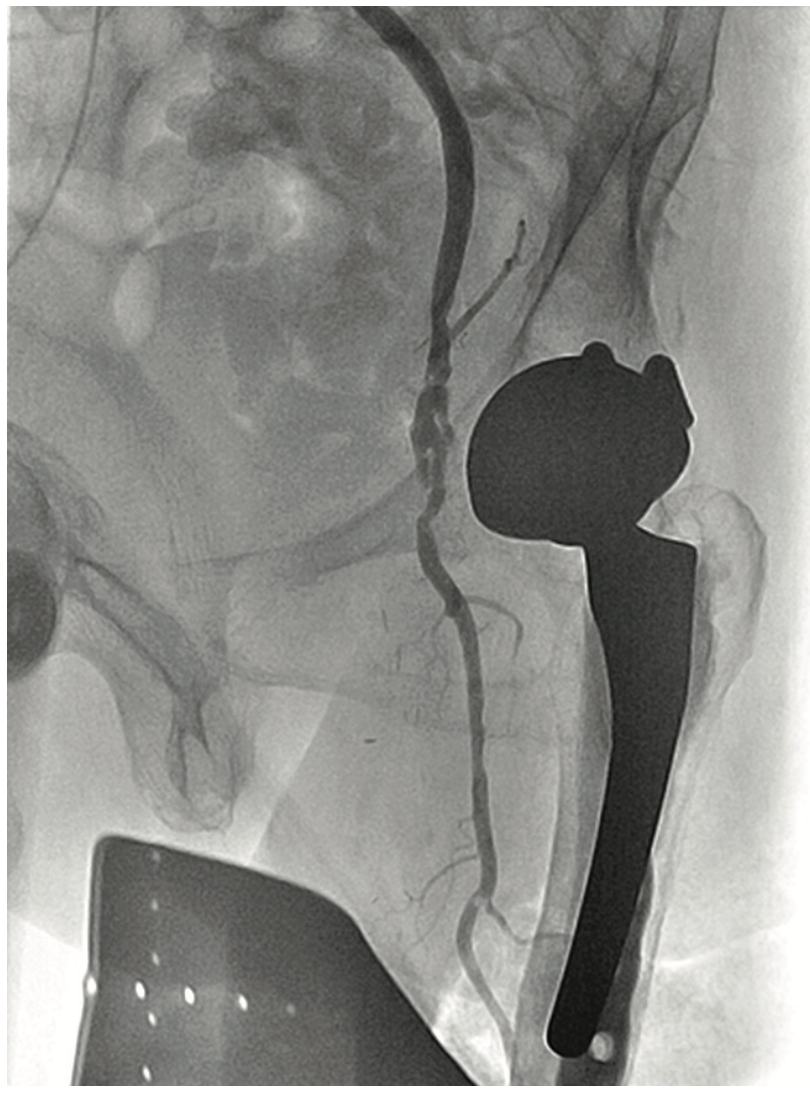

A 90-year-old woman presented with CLI of her left foot. She suffered from claudication beginning 12 years ago. Six months prior, she developed an ulcer on her foot and shortly thereafter, underwent femoral popliteal bypass. Her symptoms recurred and repeat fem-pop surgery was performed at that time. It immediately failed and she had a cadaveric vein placed as a fem-pop conduit, which again occluded and after two revisions of the fem-pop bypass, she was told five months prior to her current presentation that she would not be able to have any further intervention on her leg. At that time, it was suggested she go to hospice. A medial 1 cm x 6 cm foot ulcer was noted on examination, but the patient refused any intervention. Six weeks later, with insistence from the wound care center, and with the patient’s second and third digit now black on that foot, the patient permitted an evaluation for possible limb salvage. The examination showed that the foot was now cool and the second, third, and fourth digits were bluish-black. No pedal pulses were present. The patient was approached via the contralateral groin, and the angiogram revealed her native SFA and graft to be occluded at the origin (Figure 8). With the thought that there was a likelihood of thrombus in the vessel, we utilized the CrossLock LP and crossed the occlusion down to the tibial vessels with a Command wire (Abbott Vascular) wire (Figures 9-10). With some suggestion of thrombus in the digital arteries, 3 mg of tPA was administered locally. A .9 laser was used and subsequent balloon angioplasty was performed using embolic protection (Figures 11-12). The fluoroscopic time was 25.2 minutes and contrast was 273 cc. At the end of the procedure, the patient had 2-vessel infrapopliteal flow and several hours later, was seen by the orthopedic surgeon for metatarsal surgery. The surgeon stated that all the toes were now pink, the patient had palpable pedal pulses, and although it was very likely that some amount of amputation may be necessary in the second and third toe, nothing was removed, and the patient was discharged the next day.